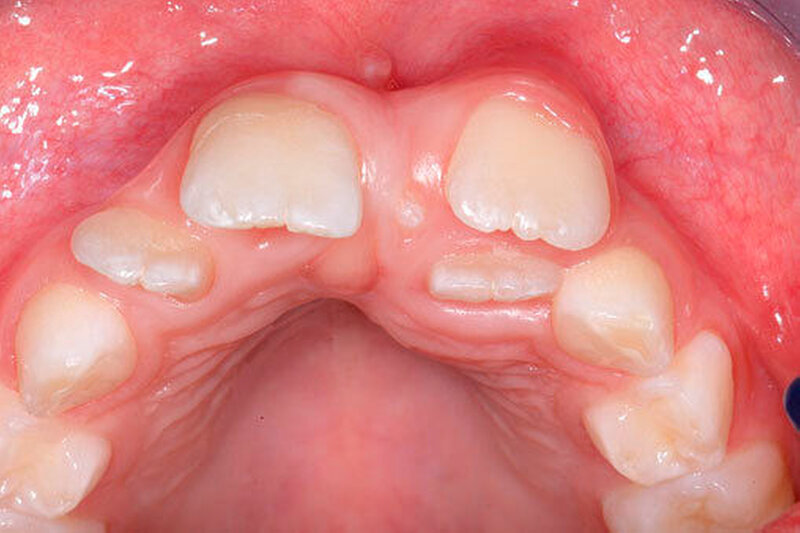

Die Prävalenz überzähliger Zähne wird im Bereich von 0,07 Prozent bis 0,6 Prozent für das Milchgebiss [Luten, 1967; Ravn, 1971; Järvinen Lehtinen, 1981; Magnússon 1984; Skrinjari Barac-Furtinovi, 1991; Yonezu et al., 1997; Chen et al., 2010] und von 0,3 Prozent bis 3,2 Prozent für die bleibenden Zähne [Luten, 1967; Bäckman Wahlin, 2001; Salcido-García et al., 2004; Leco Berrocal et al., 2007; Gündüz et al., 2008; Yagüe-García et al., 2009; Schmuckli et al., 2010; Fardi et al., 2011] angegeben. Die Mehrheit der überzähligen Zähne im Milchgebiss sind seitliche Schneidezähne im Oberkiefer, die meist mit einer normalen Morphologie und Lage durchbrechen (Abbildungen 1 bis 3) [Luten, 1967; Humerfeld et al., 1985; Garvey et al., 1999; Ferrés-Padró et al., 2009]. Der oft ungestörte Durchbruch und das Ausbleiben von Symptomen führen dazu, dass überzählige Zähne in der Milchdentition oft gar nicht diagnostiziert werden, und dies wird auch als Erklärung für die unterschiedlichen Prävalenzen überzähliger Zähne im Milch- und bleibendem Gebiss angeführt [Wang Fan, 2011]. Überzählige Zähne sind häufiger bei Männern als bei Frauen, wobei über ein Verhältnis von 1,18:1 bis 4,5:1 berichtet wird [Rajab Hamdan, 2002; Fernández Montenegro et al., 2006; Gündüz et al., 2008; Wang Fan, 2011]. In der Schweiz publizierten von Arx (1990) und Schmuckli und Mitarbeiter (2010) Geschlechterverhältnisse von 2,6:1, beziehungsweise 2,75:1. In einer aktuellen Arbeit von Mossaz und Mitarbeiter (2014) von Patienten aus dem Raum Bern lag dieses Verhältnis etwas ausgeglichener bei 1,61 zu 1.

Die überzähligen Zähne mit identischer Zahnform finden sich normalerweise beim oberen seitlichen Schneidezahn. Zusätzliche Prämolaren und Molaren können aber auch auftreten. Die Mehrheit der überzähligen Zähne im Milchgebiss sind vom identischen Zahnform-Typ und bleiben nur selten impaktiert oder retiniert.